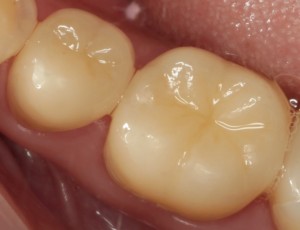

シーラント処置後

虫歯のなりかけであれば再石灰化と言われる歯の再生も見込めるので、むやみに歯を削らず、定期検診で歯の状態をチェックしていきます。